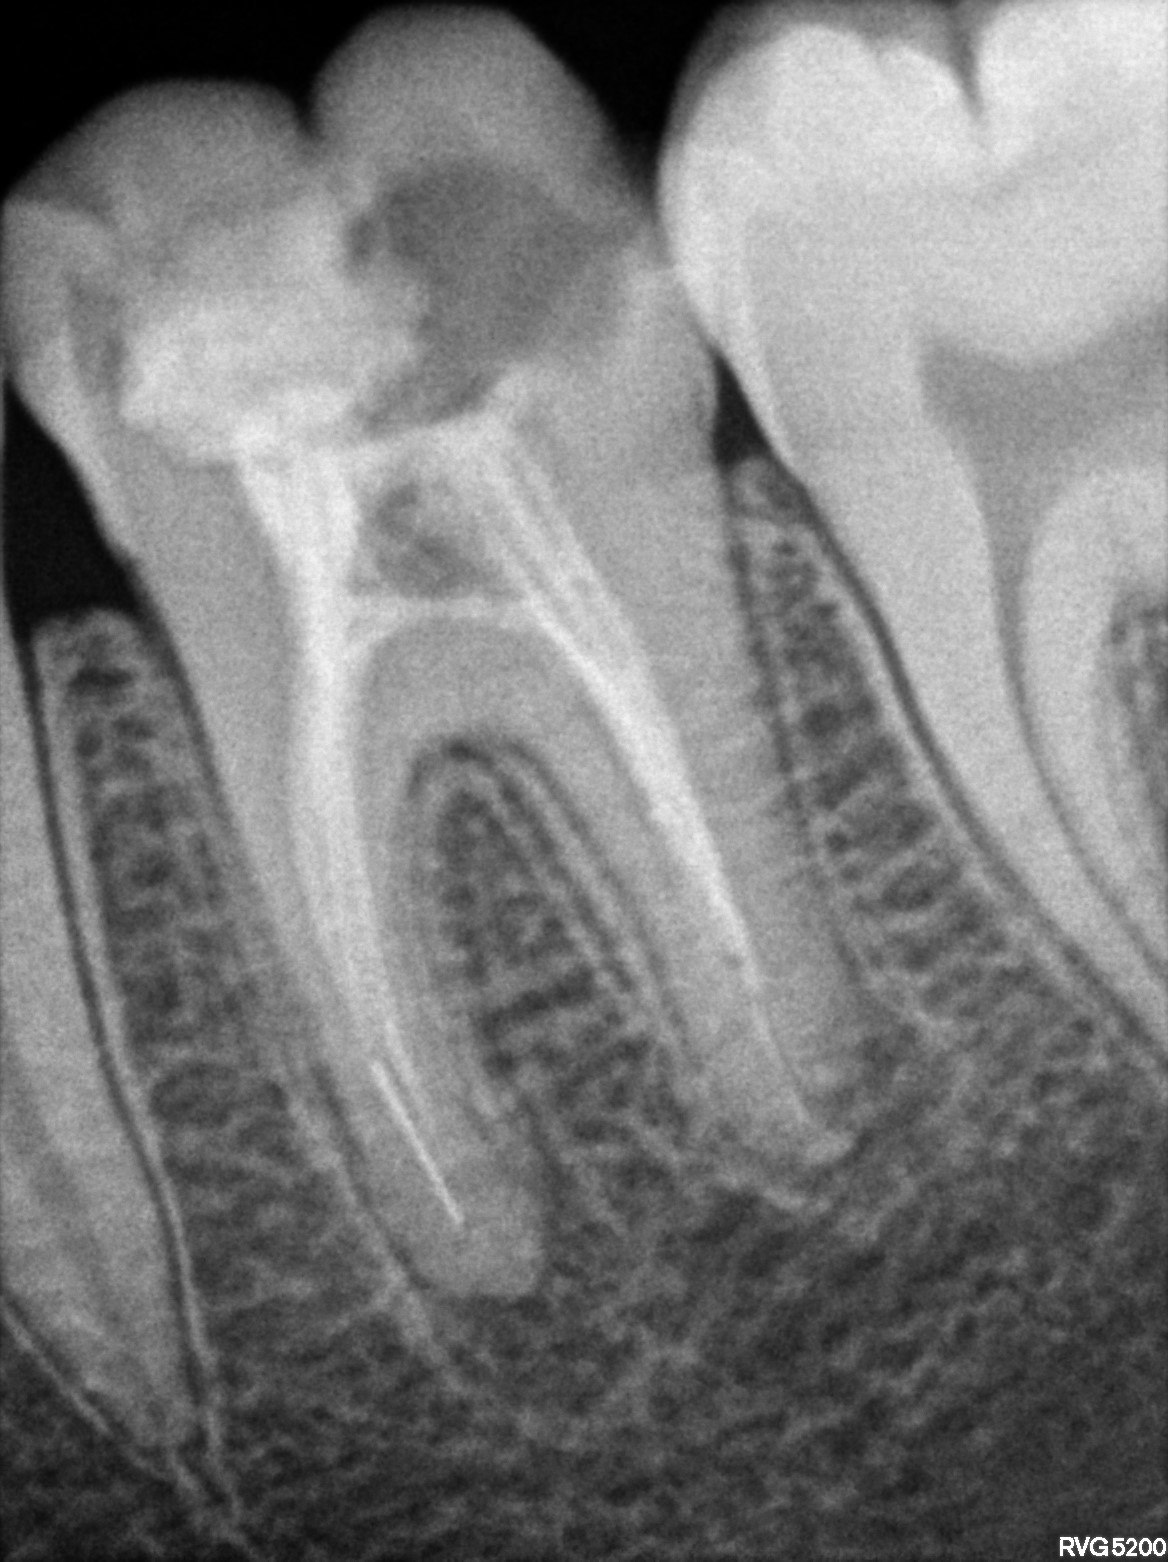

Dental Radiographs FHIR: DocumentReference · LOINC 24641-7

R58.jpg

24641-7